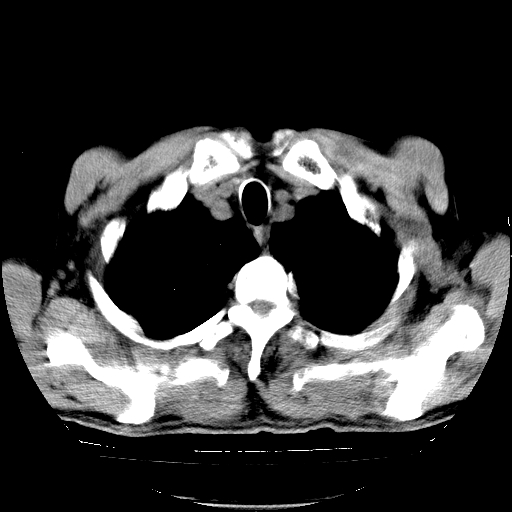

以下是引用hhcckk在2009-1-1 15:38:00的发言:[br]左下肺少许絮状模糊影--考虑感染[br]两肺散在小点状密度增高影--结合病史考虑矽肺?[br]气管壁钙化--可能由于老年退变性引起的